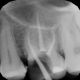

Rentgenowskie zdjęcie będzie także potrzebne czy wręcz niezbędne podczas przygotowań do leczenia kanałowego. Dzięki zdjęciu RTG lekarz będzie w stanie prawidłowo ocenić różne parametry zęba takie jak długość korzenia czy ilość kanałów.